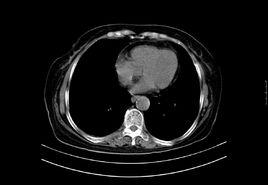

白血病,又叫血癌,當人們患有白血病,特別是患有急性白血病時,胸骨壓痛便成為重要的體徵之一。據臨床觀察,多數病人胸骨壓痛最明顯的部位在胸骨下部,即相當於第四、第五肋間的胸骨部。醫學家們認為,產生骨痛的原因主要是由於骨髓內白血病細胞大量增殖,引起骨髓腔容積壓力增高,以及白血病細胞浸潤骨膜刺激感覺神經而引起。從解剖學上看,胸骨板很薄,覆蓋此部的皮膚也很薄,骨膜感覺神經也較豐富,所以,對觸壓很敏感,往往會產生明顯的壓痛。

胸骨下部,即相當於第四、第五肋間的胸骨部壓痛。是白血病特別是急性白血病的重要體徵之一。同時也可見於惡性淋巴瘤、骨髓增殖性疾病,但後兩者較為少見。